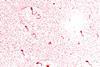

A study, led by Dr Xin Zhou, Prof. Sybren de Hoog (Radboud UMC Center of Expertise for Mycology, Netherlands), and Prof. Peiying Feng (Sun Yat-Sen University, China), revealed that while M. canis, M. audouinii, and M. ferrugineum share a high degree of genetic similarity, human-adapted strains exhibited specific expansions in gene families, such as Major Facilitator Superfamily (MFS) transporters and Zn2Cys6 transcription factors. These gene expansions may enhance the fungus’s ability to thrive in the human skin environment.

Genetic diversity and functional studies identified 12 key genes, including proteases (e.g., SUB1, SUB7, PRB1) and chitinases (e.g., Arb2, MCYG_06206). These genes play crucial roles in keratin degradation, immune evasion, and environmental adaptation. For example, the expression of subtilisins (SUB1-SUB3) of anthropophilic species increased significantly under acidic conditions, such as those found on human skin. In addition, lipid-rich environments further stimulated keratinase activity, suggesting that these factors drive host-specific adaptations in human-derived M. canis strains.

Further analyses revealed that carbohydrate metabolism genes, including those involved in chitin-binding and degradation, have undergone significant expansion in M. canis. These genes may enable the fungus to evade host immune responses by masking fungal cell wall components. Comparative genomic studies also showed that lineage-specific differences in gene duplication events correlate with ecological and physiological adaptations across host types.